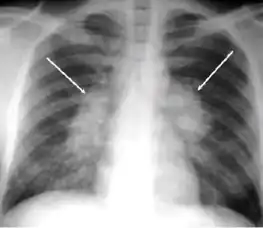

-

Chest x-ray showing bilateral hilar adenopathy of primary pulmonary TB